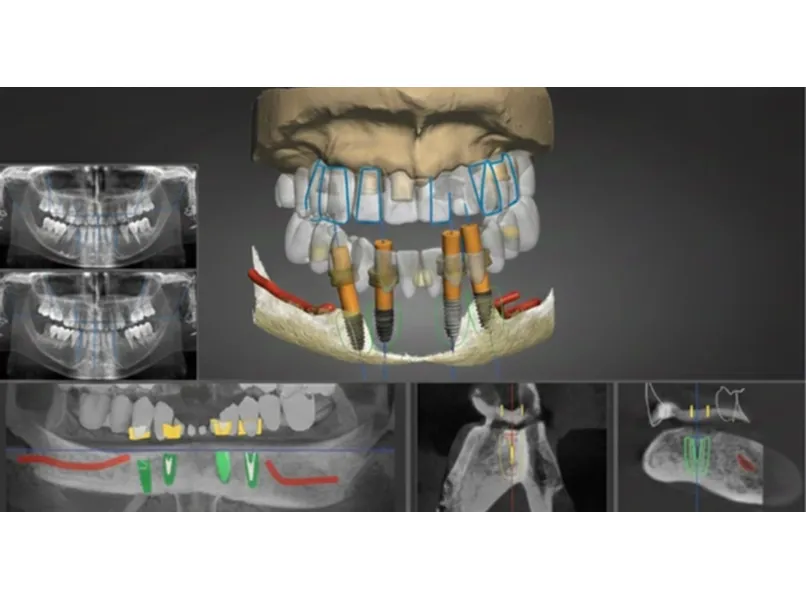

精密CT、3Dシミュレーションで 正確な骨の状態を分析します。

精密診断

カスタマイズ設計

審美補綴との調和を考慮し 機能と審美を反映した 治療計画を立てます。